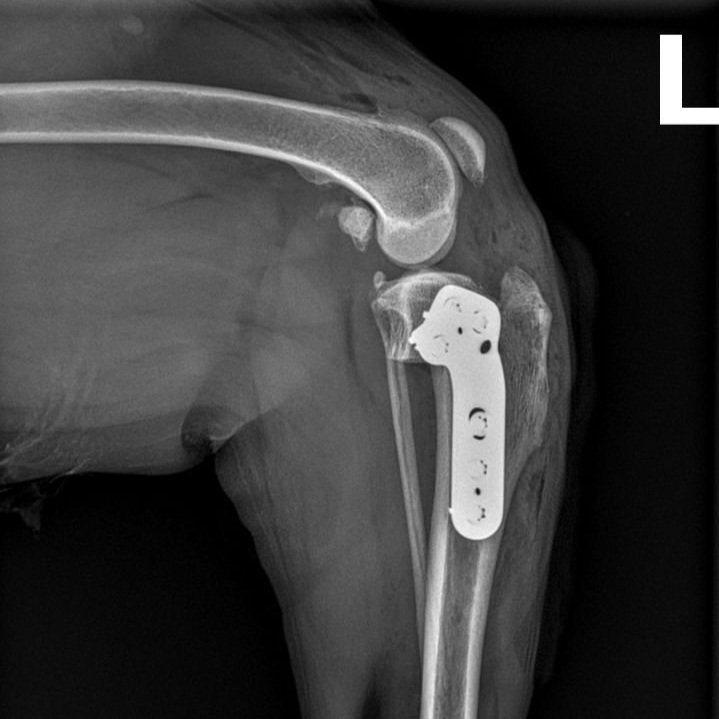

• Kreuzbandrissversorgung mit Tibial Plateau Leveling Osteotomy (TPLO)